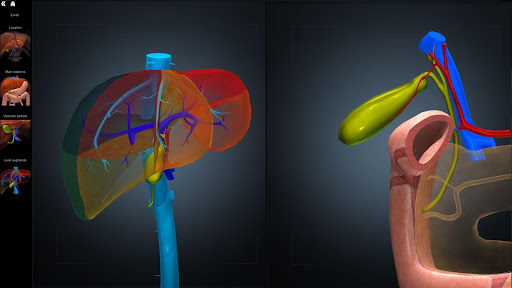

A true and totally 3D app for studying human anatomy, built on an advanced interactive 3D touch interface.

★ Digestive